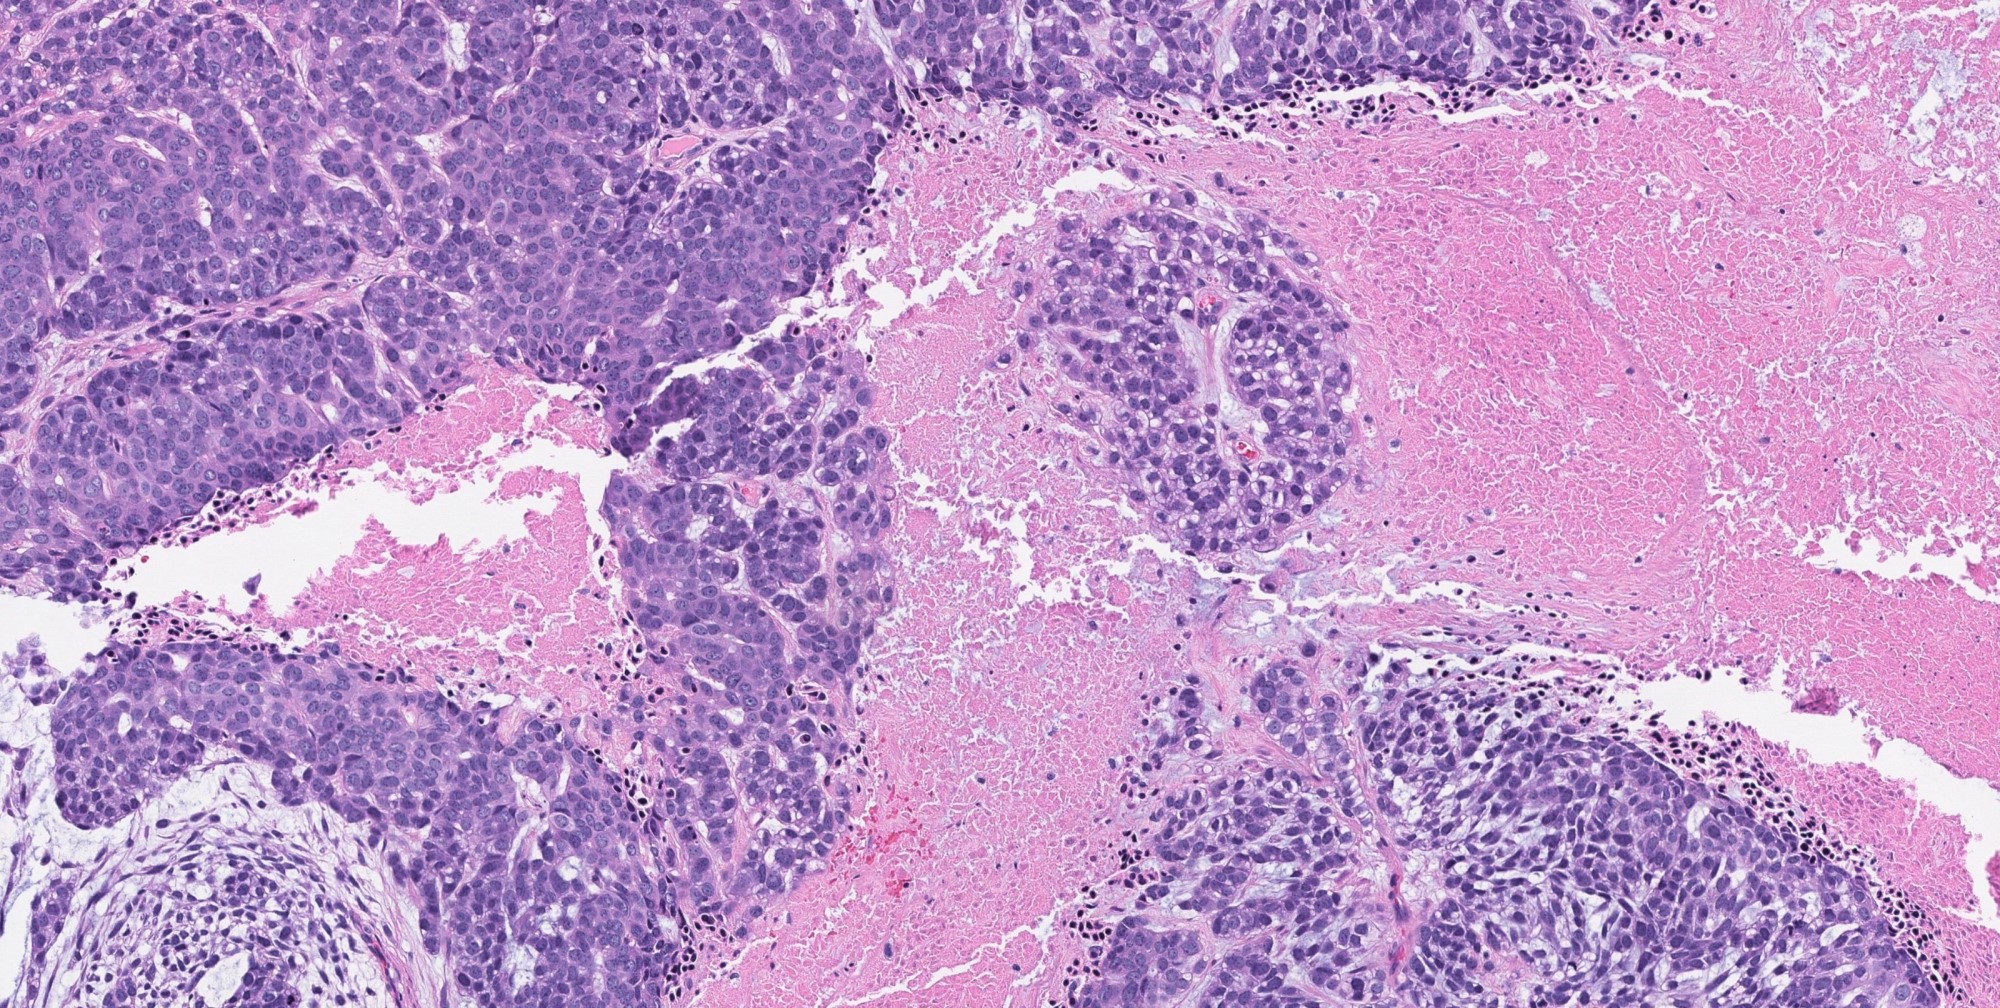

- Invasiveness is typically demonstrated as expansile invasive multinodular growth: myoepithelial carcinoma rarely shows infiltration of single cells / small clusters or desmoplastic reaction

- Nodules often have a hypocellular center with hyalinized stroma or bland necrosis surrounded by a hypercellular peripheral zone

- Composed (near) entirely of myoepithelial cells showing various cytologic features, including clear cell, epithelioid, plasmacytoid or spindle cell morphology

- Common architectural patterns include solid, trabeculae, cords, nests and single cells

Contributed by Abeer Salama, M.D. and Bin Xu, M.D., Ph.D.